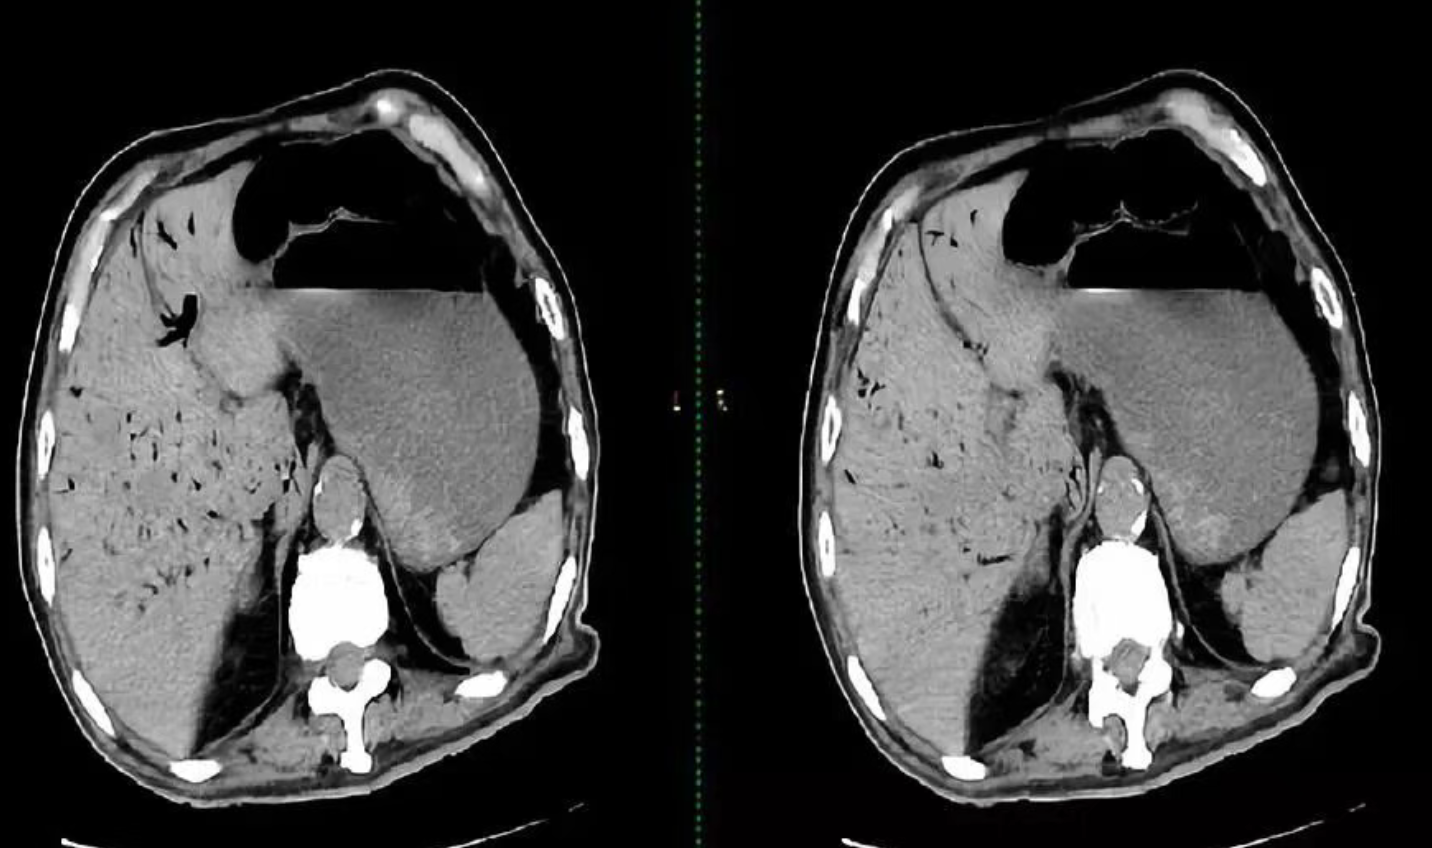

【医学名词解释】枯树征: 是一种在腹部 CT 影像上呈现的特征性表现,,在影像上呈现出类似枯树枝的分支状透亮影而得名,也被称为门静脉积气征(Hepatic Portal Venous Gas)。这是一个极其凶险的影像学征象,预示着极高的死亡率。